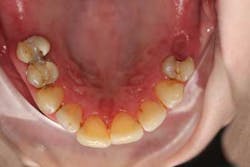

After a complete assessment, it was apparent that Sara’s options were limited with her existing dentition. The caries present were large and apple-cored around the teeth, making the long-term restorative prognosis questionable or guarded at best (figures 2-5). Several key teeth for partial abutments were either missing or grossly carious.

Options were discussed at a consultation appointment: full/full, partial/full, partial/partial (not ideal), or the use of implants. Two things were apparent at that consultation: (1) She didn’t want dentures. (2) Finances were such that they dictated her ultimate decision, because fixing and maintaining her teeth long term were things she just couldn’t afford. She recognized the fact that her health and subsequent need for medications were just one of the factors contributing to her current situation, and she couldn’t foresee that getting better in the near future. Sara, therefore, opted to go with double-arch full/full dentures; she made her decision knowing that dentures would present her with a new set of challenges. Because her lower teeth were bothering her the most, we commenced treatment on the lower arch, with plans to proceed with the maxillary at a later date.